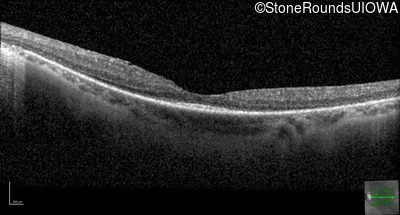

Optical Coherence Tomography - Right - 20/30 +2

Exemplar / OCT Stack